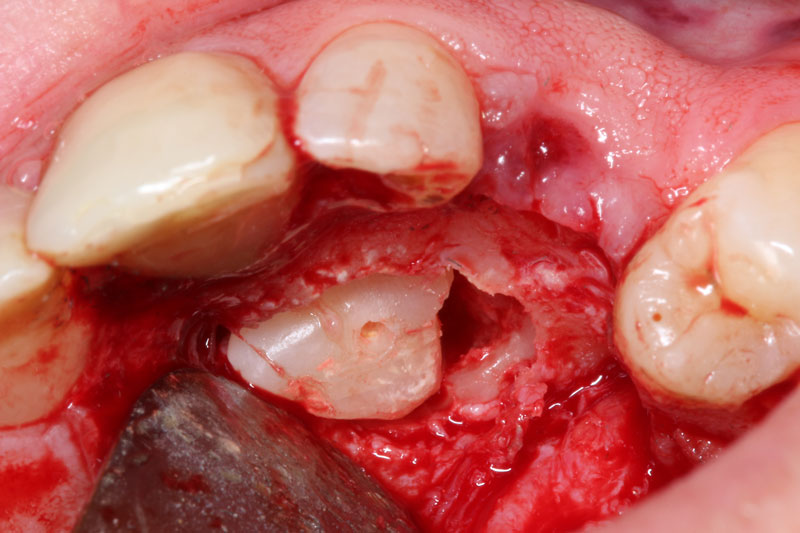

2. χειρουργικη αφαίρεση εγκλείστων οδόντων ιδιαίτερης δυσκολίας

3α. χειρουργικη των λοιπών εγκλείστων οδόντων

- Χειρουργικη εγκλείστων 3ων γομφίων μέσης -αυξημένης δυσκολίας

- Χειρουργική αποκάλυψη εγκλείστων δοντιών για ορθοδοντικούς σκοπούς.